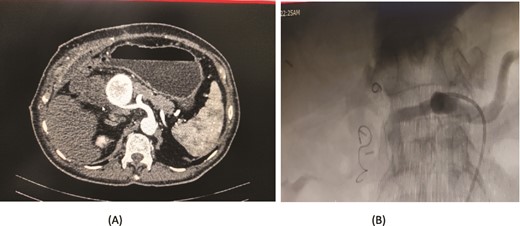

A 66-year-old male underwent an extended cholecystectomy with bile duct excision and Roux-en-Y hepaticojejunostomy for suspected gallbladder carcinoma. However, the histopathological examination revealed xanthogranulomatous cholecystitis. Postoperative patient develops anastomotic site leakage so was discharged with abdominal drain. On the 9th postoperative day, during follow-up for bile leak with an abdominal drain in situ, a contrast-enhanced CT scan of the abdomen identified a pseudoaneurysm at the bifurcation of the gastroduodenal artery and proper hepatic artery. Angioembolization was performed using two coils and 50% glue. The abdominal drain was subsequently removed, and the patient recovered without further complications, doing well at follow-up (Fig. 4).

Case 4. (A) CT scan – pseudoaneurysm at bifurcation of gastroduodenal artery and proper hepatic artery. (B) Embolization of gastroduodenal artery and proper hepatic artery.